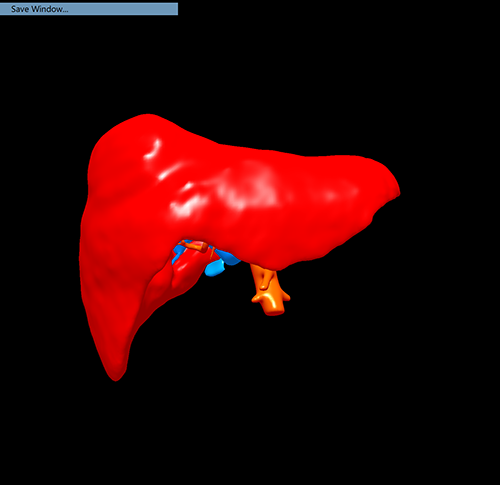

右肝癌---右三肝切除

介入后2周